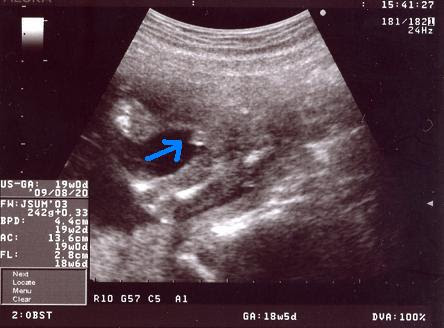

胎児エコー動画 妊娠18週1日 性別判断 Youtube

胎児エコー動画②:妊娠18週1日 性別判断 Watch later Share Copy link Info Shopping Tap to unmute If playback doesn't begin shortly, try restarting your device Up Nextお腹が前に出てきたら男の子、横に出てきたら女の子? 昔から言われているのが「お腹が前に出てきたら男の子、前でなく横に出てきたら女の子」という性別ジンクス。 今でも、周囲の人から、お腹を見て女の子か男の子かを言われている妊婦さんも多いようですが、このジンクスに医学的根拠はありません。 超音波検査もない時代は、今以上に赤ちゃんの性別が

19w3d 妊婦検診 胎児スクリーニング検査 そして性別判明 双子ママの妊娠 出産 育児ブログ

妊娠19週目 胎動や性別が分かる人も 胎児のエコー写真 大きさ 妊娠中期 All About

医師監修 妊娠19週のエコー写真を多数掲載 みんなのエピソードつき Michill ミチル